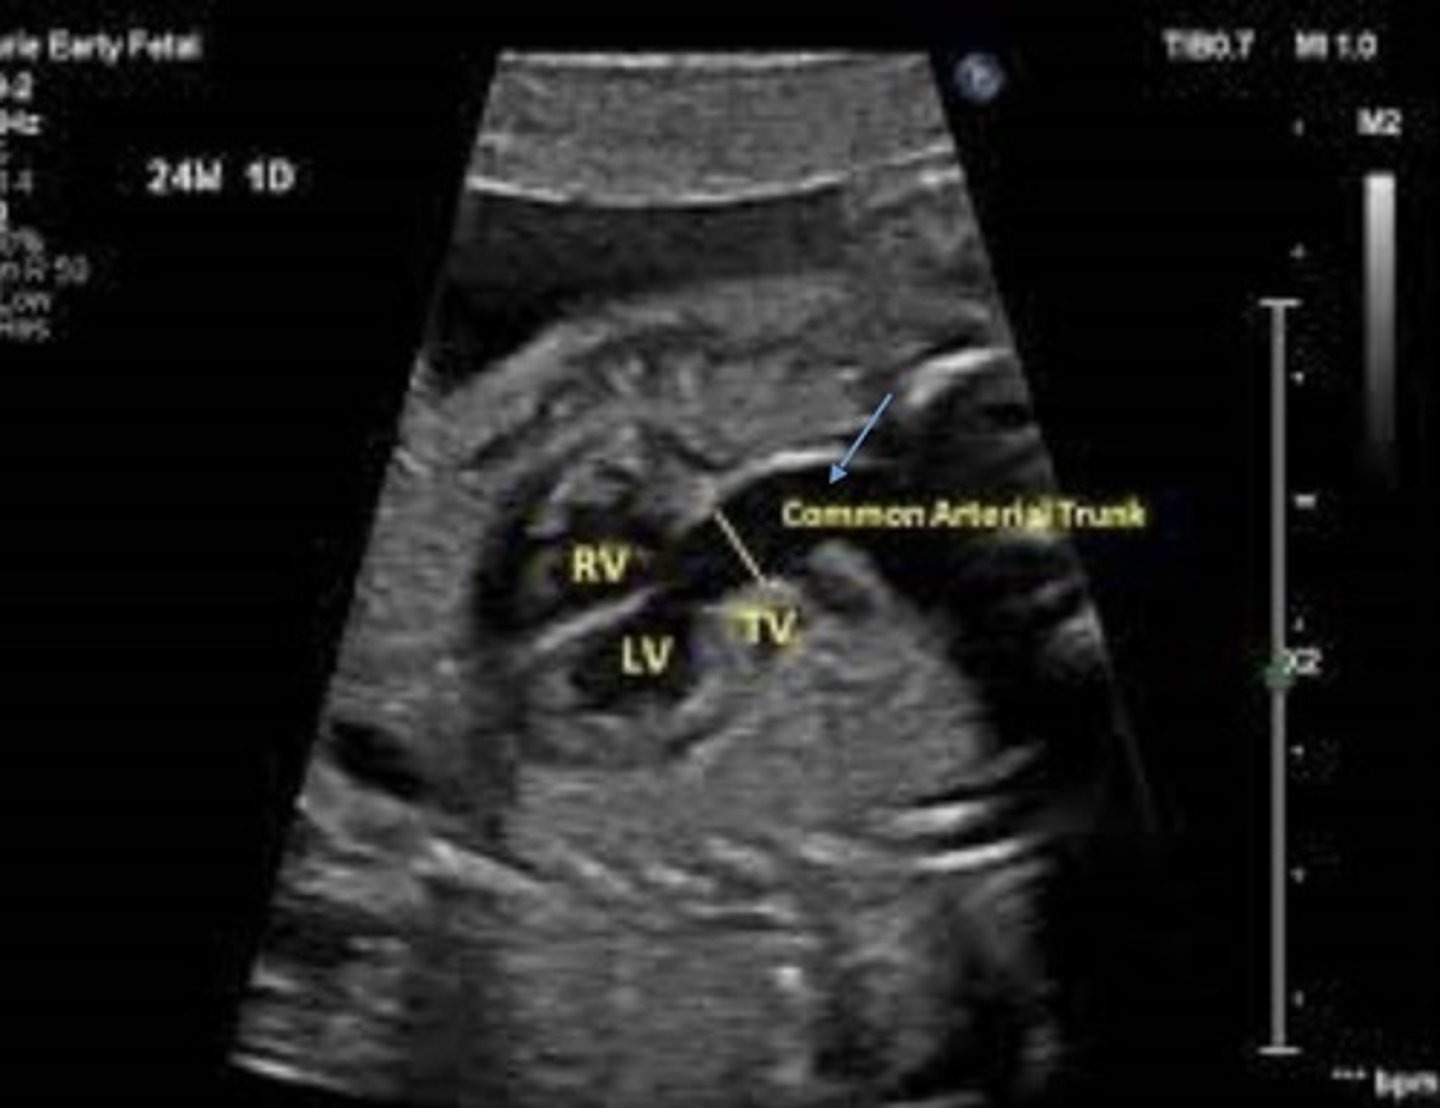

Truncus Arteriosus

Best seen in LVOT view

Truncoconal ridge fails to fuse

Appears as single great vessel with VSD